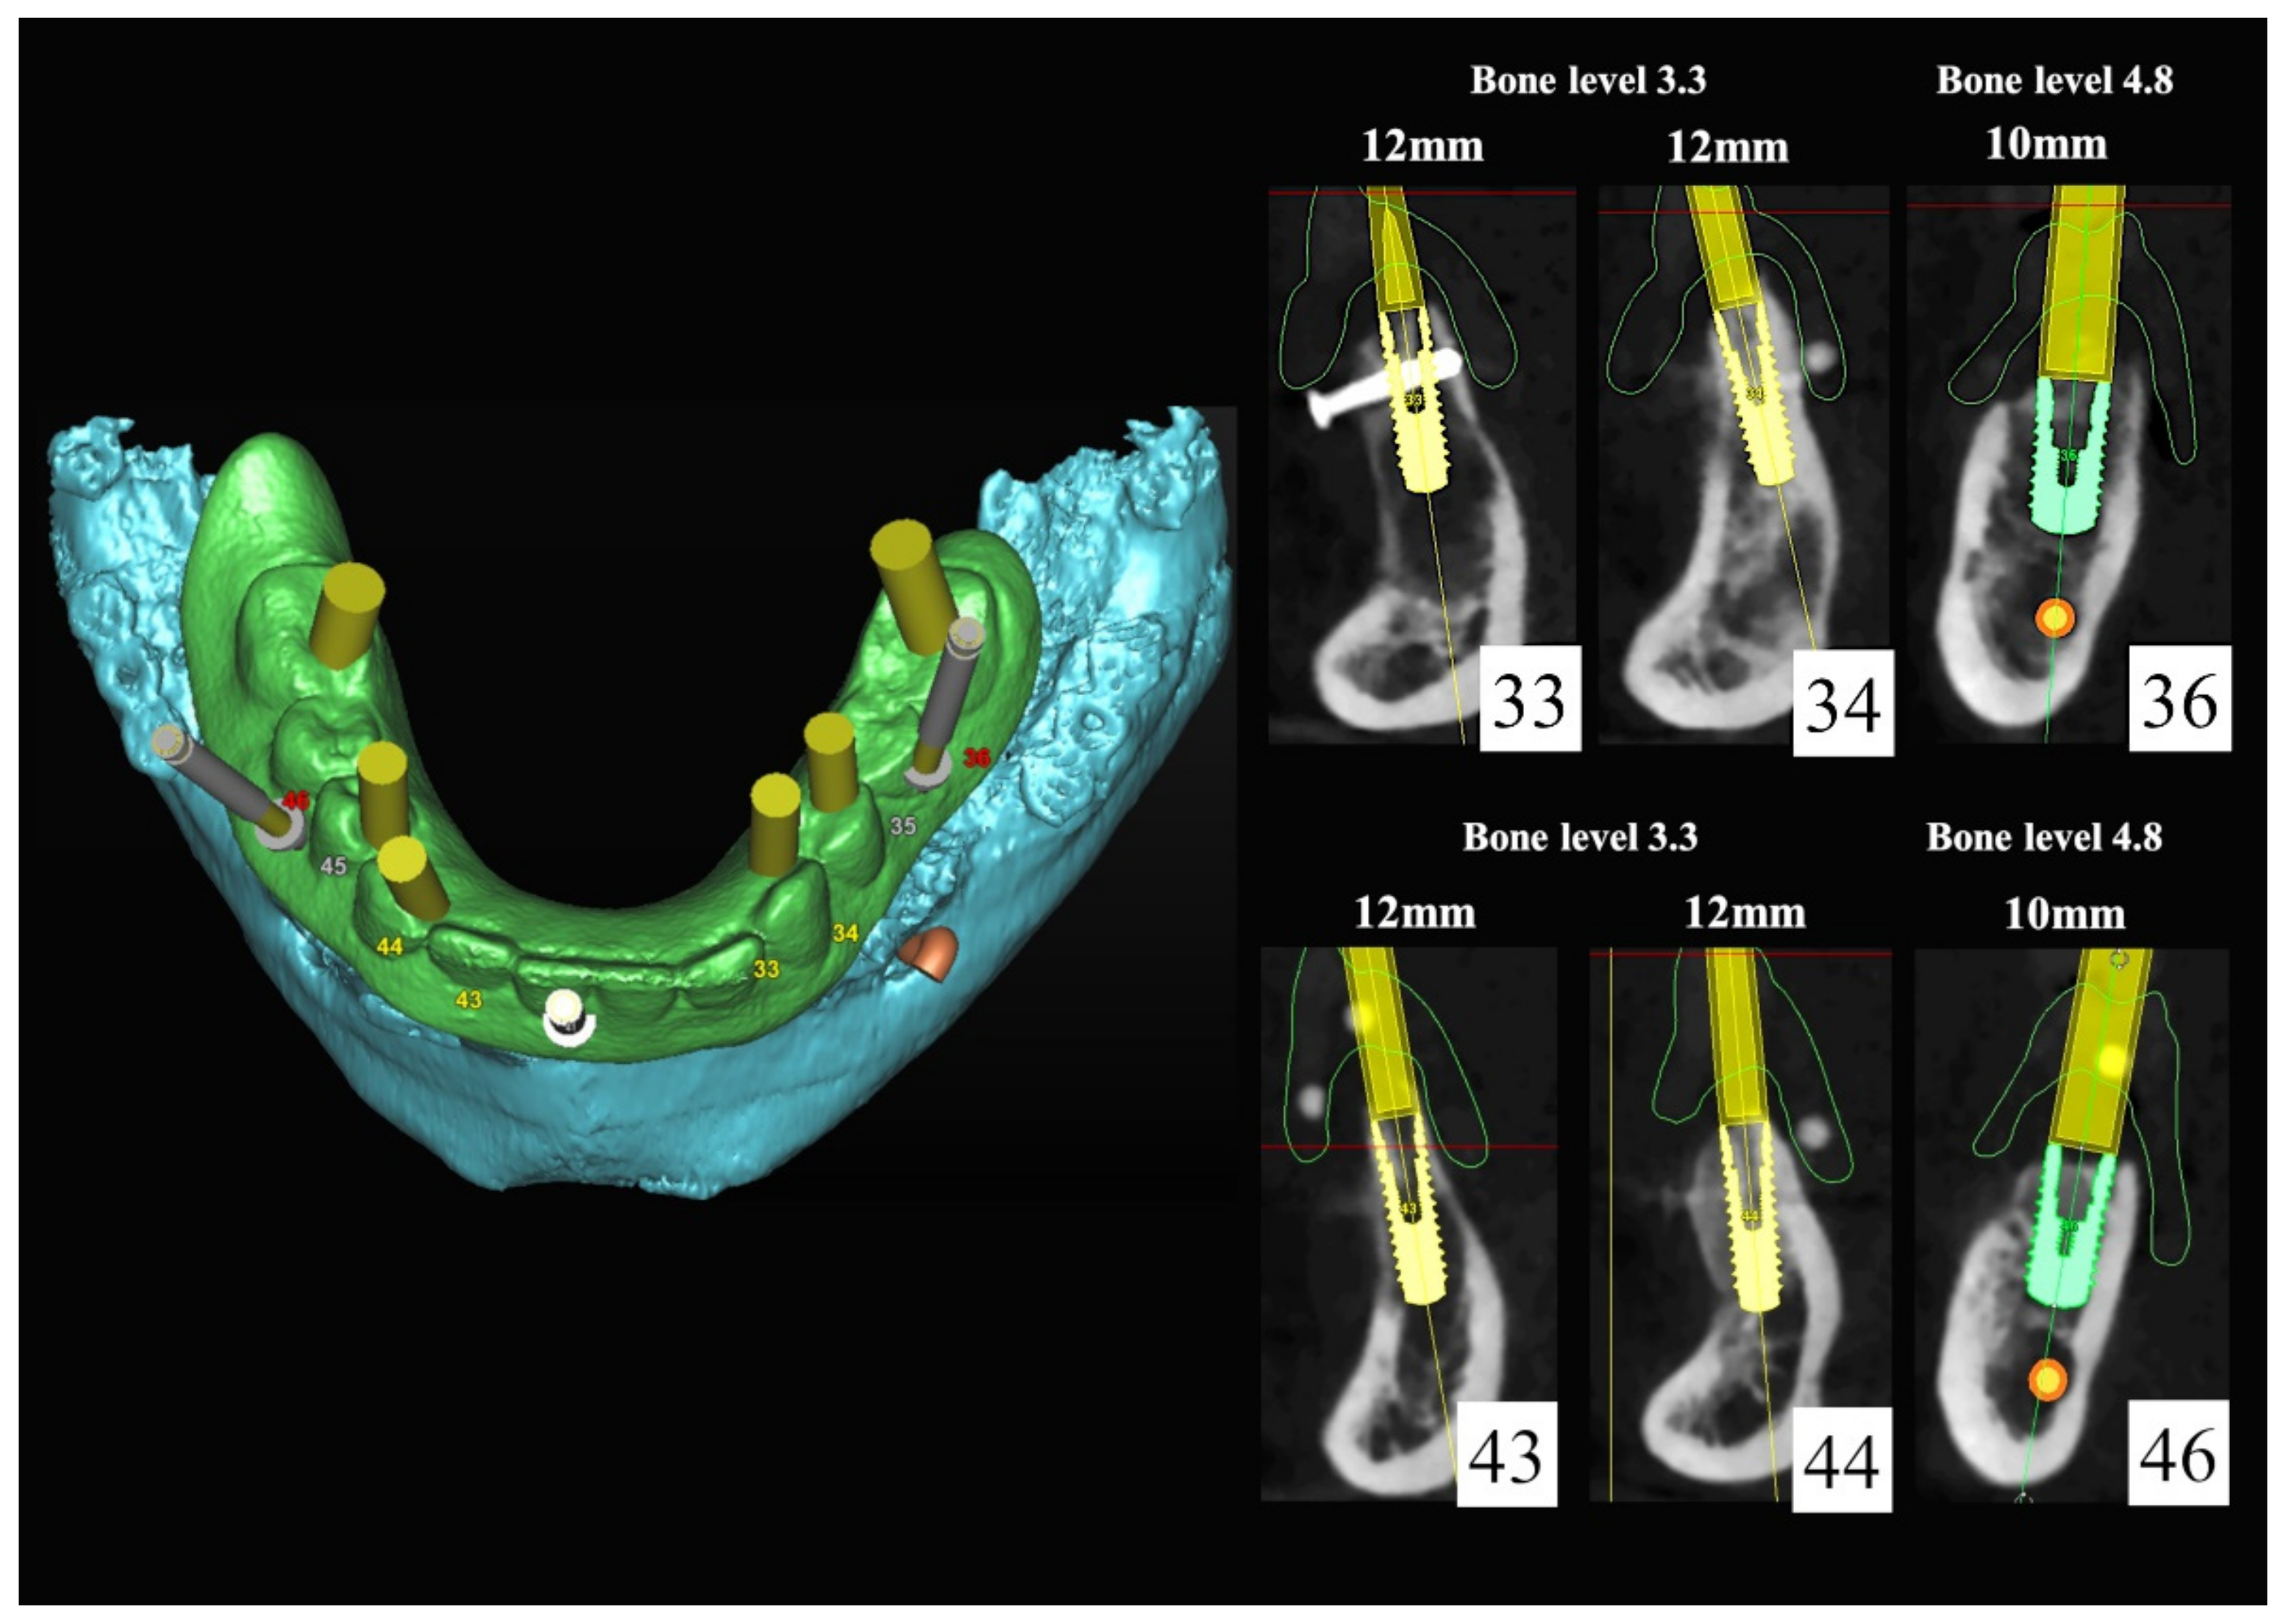

The number, the length, the diameter and the placement of computational virtual implants were determined with respect to the design of the final prosthesis the available residual bone volume and the anatomical limitations according to the previously described technical procedure (Figure 16, Figure 17, Figure 18, Figure 19, Figure 20 and Figure 21).

Figure 18.

Three-dimensional (3D) planning of the number, the diameter and the axis of dental implants with respect to the design of the final virtual maxillary prosthesis.

Figure 19.

In March 2013, twelve guided dental implants were placed at sites # 12, # 13, # 15, # 22, # 23, # 25, # 33, # 34, # 36, # 43, # 44, and # 46 (Figure 22, Figure 23, Figure 24, Figure 25 and Figure 26)